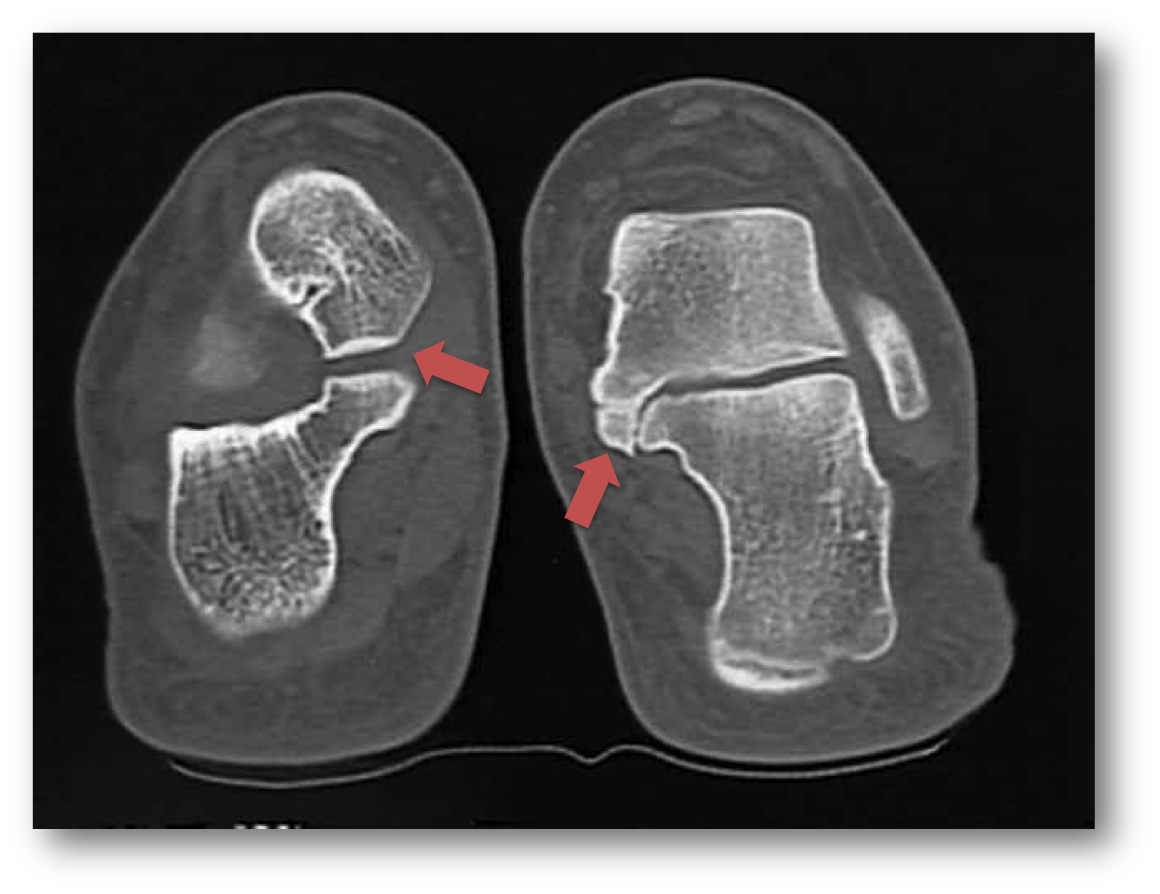

Here is an image taken from a CT scan, on the left is a normal subtalar joint, the red arrows points to it. On the right is the same joint on the patients other foot, there is no joint separation, this is a subtalar coalition.